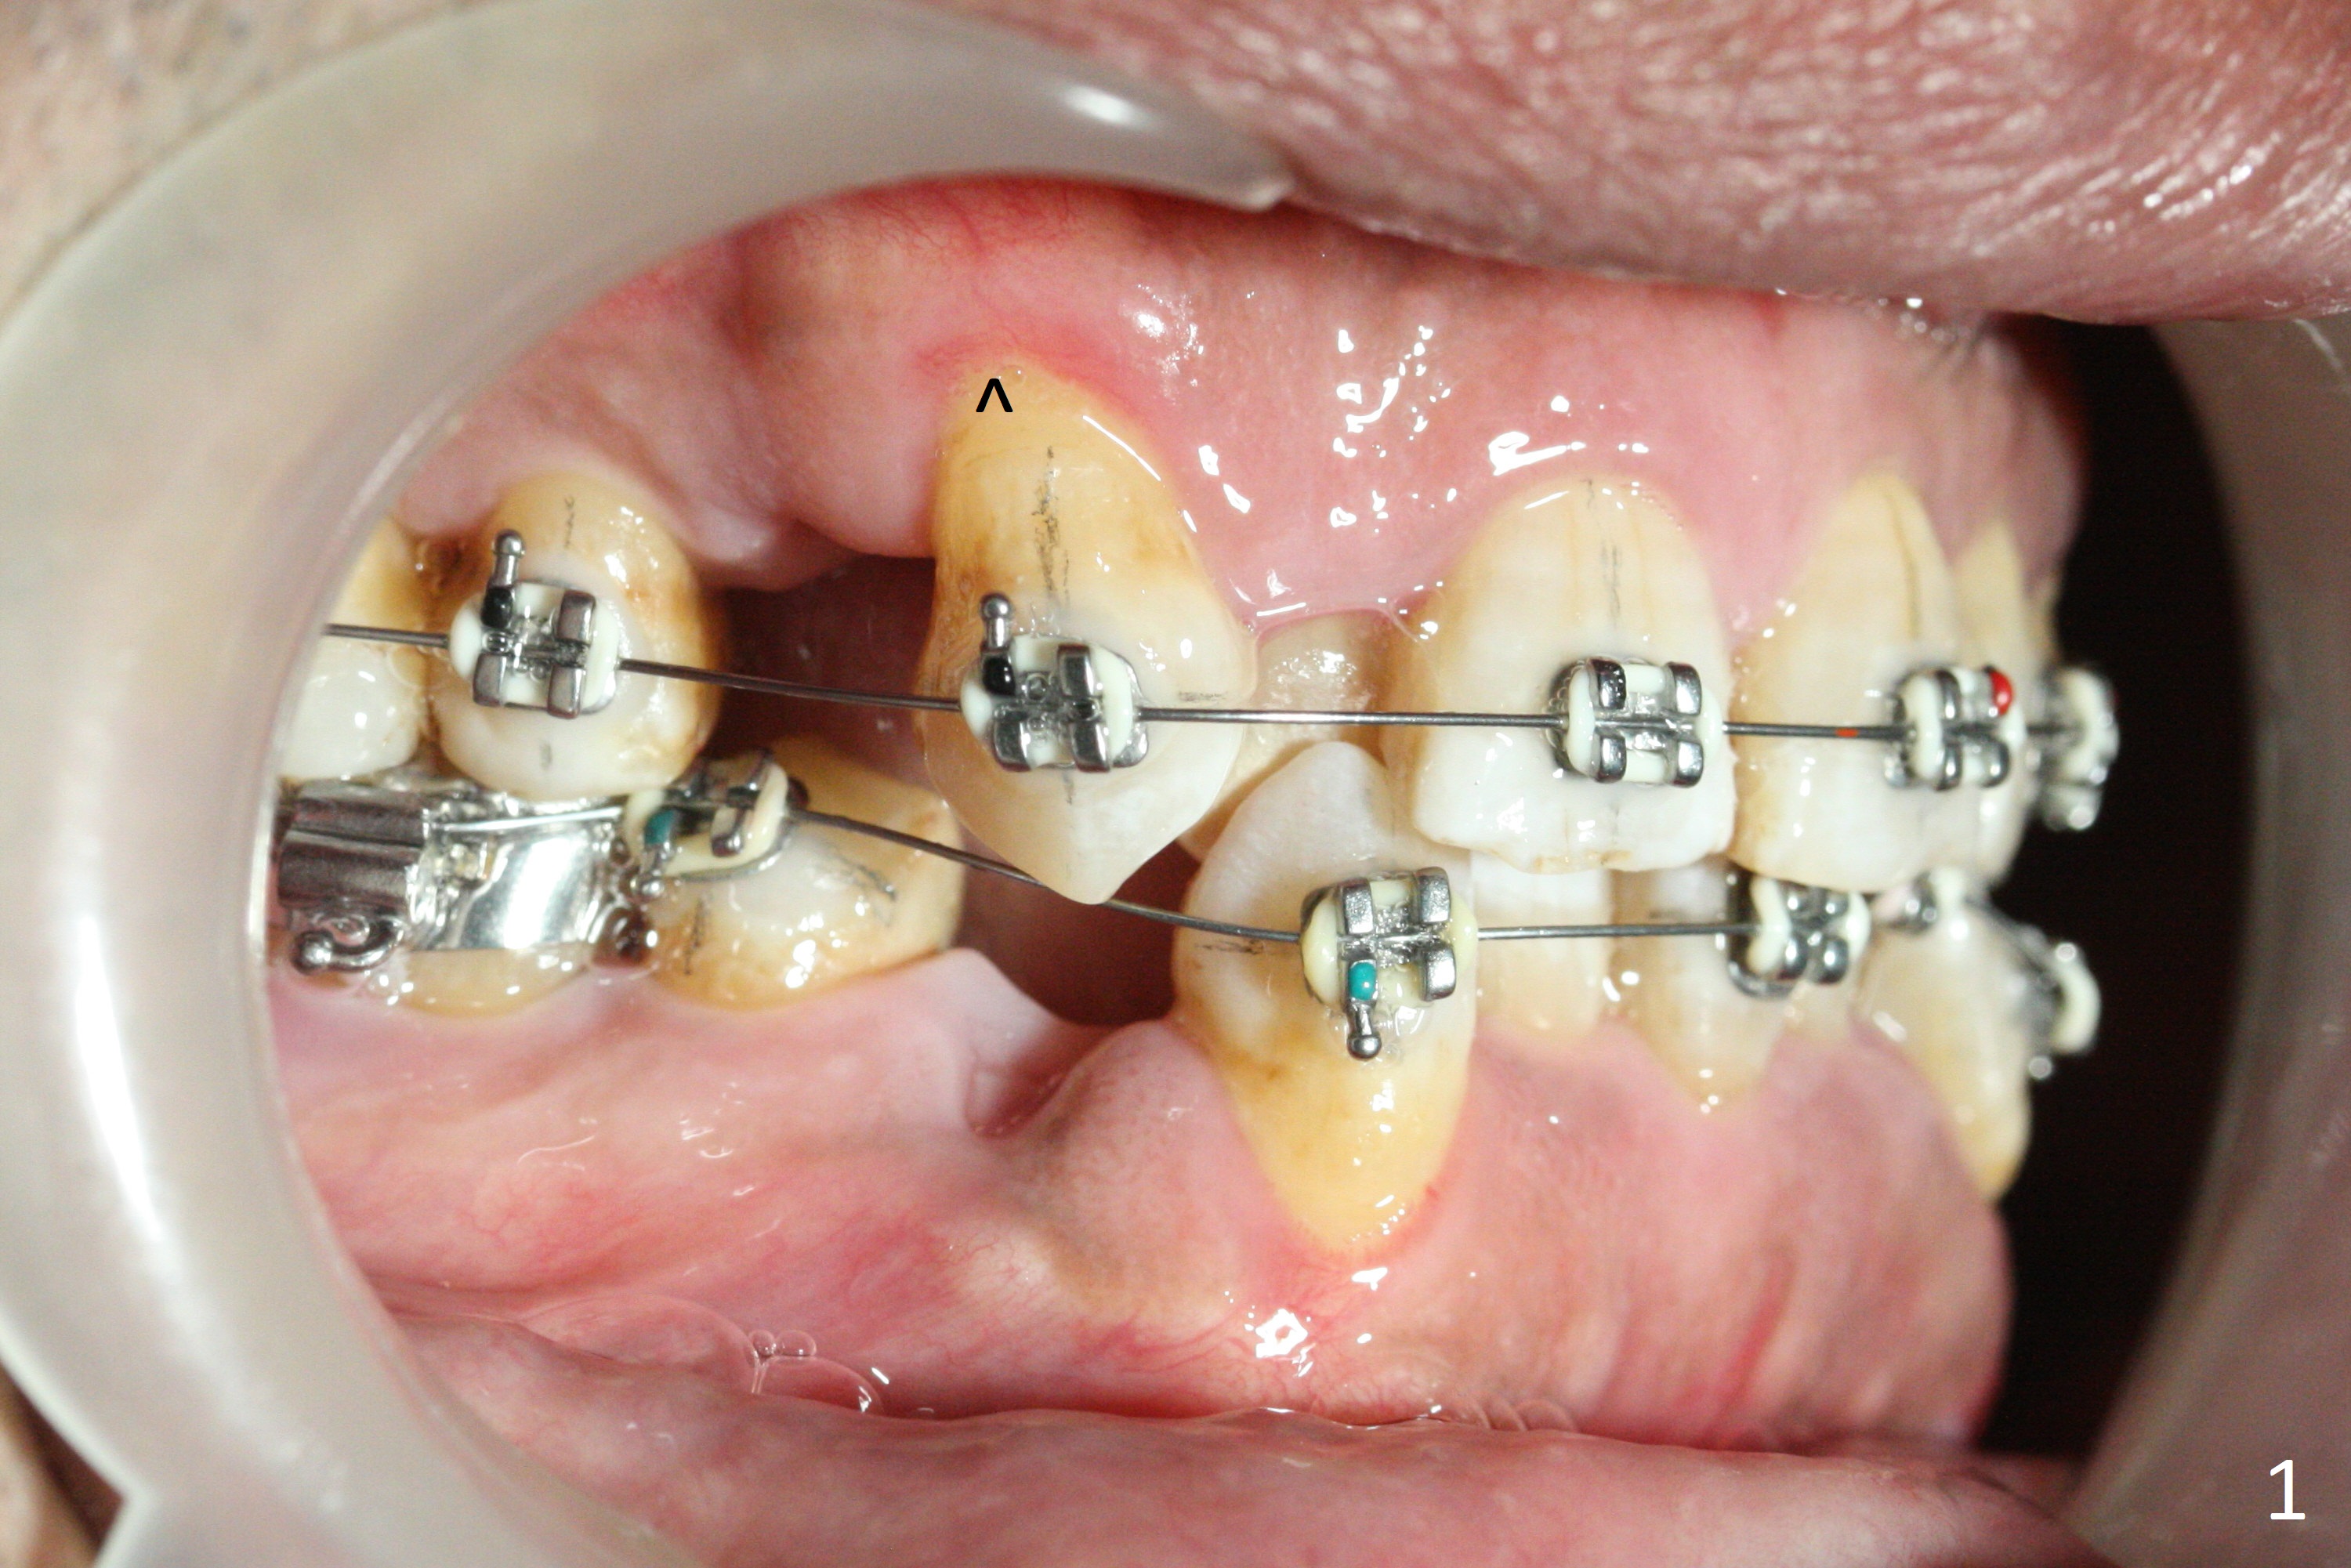

A few days post Water Pik use, the gingival erythema subsides substantially, a sign of cooperation (Fig.1 ^, as compared to earlier). Because of tight contact and loss of rubber separators due to use of water flosser, molar brackets have to be used except LR (Fig.1-3). There is enough space for UR2 bracket 5.5 months post banding. While keeping open and closed springs at UR, place sling shot for UR2. There are 2 purposes. One is to keep expanding the space for UR2, since the sling-shot tends to close the space. The second rationale is to continue mesializing UR1 to correct the upper midline deviation.

While LL3 has been distalized, there is not enough space to buccalize LL2. Extra space will be gained by continuing distalizing LR3. Consider using 7s instead of 6s as anchorage for closed springs for all of the 4 quadrants.